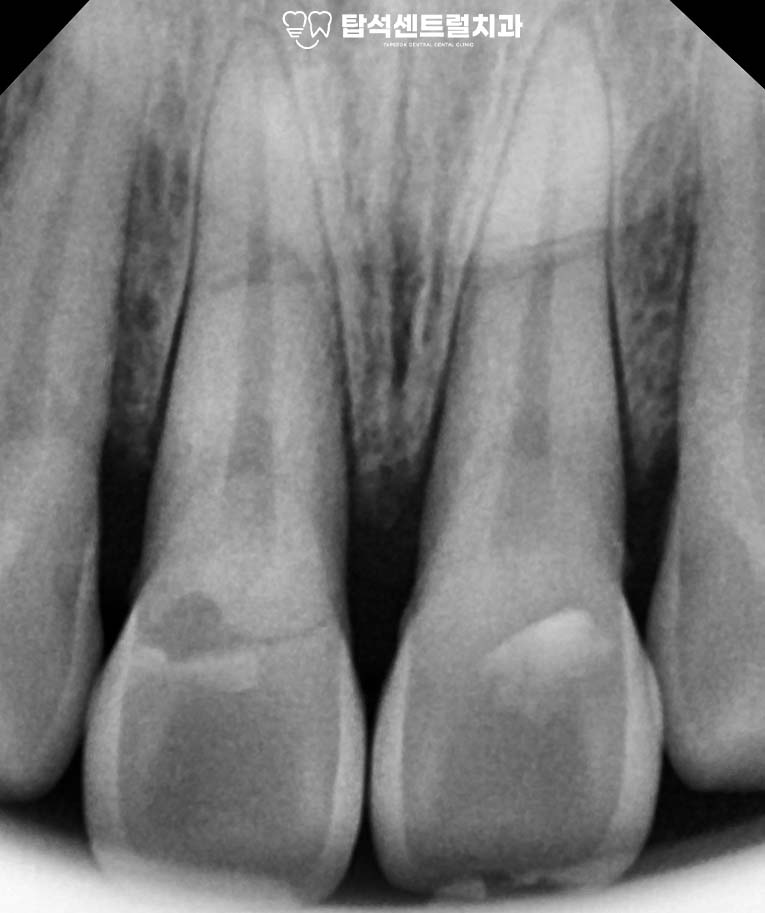

엑스레이나 CT 촬영을 통해

내부 상태를 정밀하게 확인하게 됩니다.

육안으로는 보이지 않는

미세한 균열이나 뿌리 골절을

영상 검사로 파악할 수 있습니다.

만약 심하게 동요도가 있고

주변 조직과의 연결이 끊어져

회복이 어려운 상황이라면

발치를 고려해야 될 수도 있습니다.